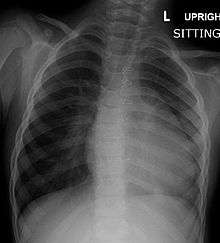

| Right ventricular hypertrophy | The right ventricle is more muscular than normal, causing a characteristic boot-shaped (coeur-en-sabot) appearance as seen by chest X-ray. Due to the misarrangement of the external ventricular septum, the right ventricular wall increases in size to deal with the increased obstruction to the right outflow tract. This feature is now generally agreed to be a secondary anomaly, as the level of hypertrophy tends to increase with age.[18] |

Before more sophisticated techniques became available, chest x-ray was the definitive method of diagnosis. The abnormal "coeur-en-sabot" (boot-like) appearance of a heart with tetralogy of Fallot is classically visible via chest x-ray, although most infants with tetralogy may not show this finding.[21] Absence of interstitial lung markings secondary to pulmonary oligaemia are another classic finding in tetralogy,[22] as is the pulmonary bay sign.